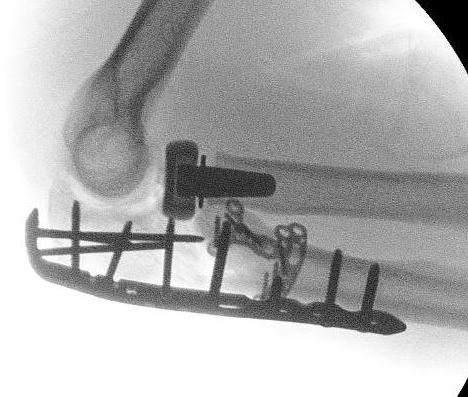

Universal posterior approach with radial head replacement and medial approach with medial buttress plate